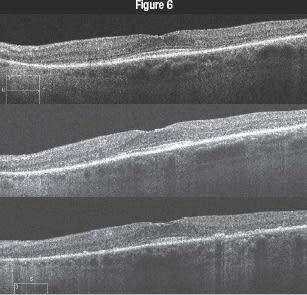

| A 70-year-old woman is evaluated for decreased vision in her left eye. She has Sjögren syndrome, posterior vitreous detachment and epiretinal membrane in both eyes and a history of pigmentary changes observed in the left eye for 6 years. She has hypertension, hypothyroidism and rheumatoid arthritis. She is taking enalapril (Vasotec), levothyroxine (Synthroid), and hydroxychloroquine (Plaquenil) (200-300 mg for 20 years). Note the mild ERM present and eventually the loss of the OS/IS junction with pigment atrophy. Owing to these changes, it was recommended the patient discontinue the Plaquenil.

On visits in July 2009, March 2010 and January 2011 (top to bottom), the patient's visual acuity OS was 20/20, 20/25−1 and 20/25+2.

On visits in July 2009, March 2010 and January 2011 (top to bottom), the patient's visual acuity OD decreased from 20/20 to 20/20−2 to 20/25−2. |